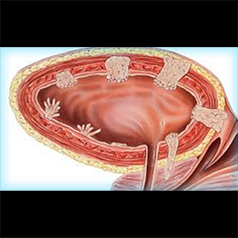

Mesane tümörleri, mesane içerisini kaplayan değişici hücreli epitelden kaynaklanan tümörlere verilen genel isimdir.

devamı için tıklayınız.Trans-Üretral Rezeksiyon-Mesane (TUR-M): Mesane tümörü patolojik tanı ve tedavisinde ilk ve en sık uygulanan yöntemdir.